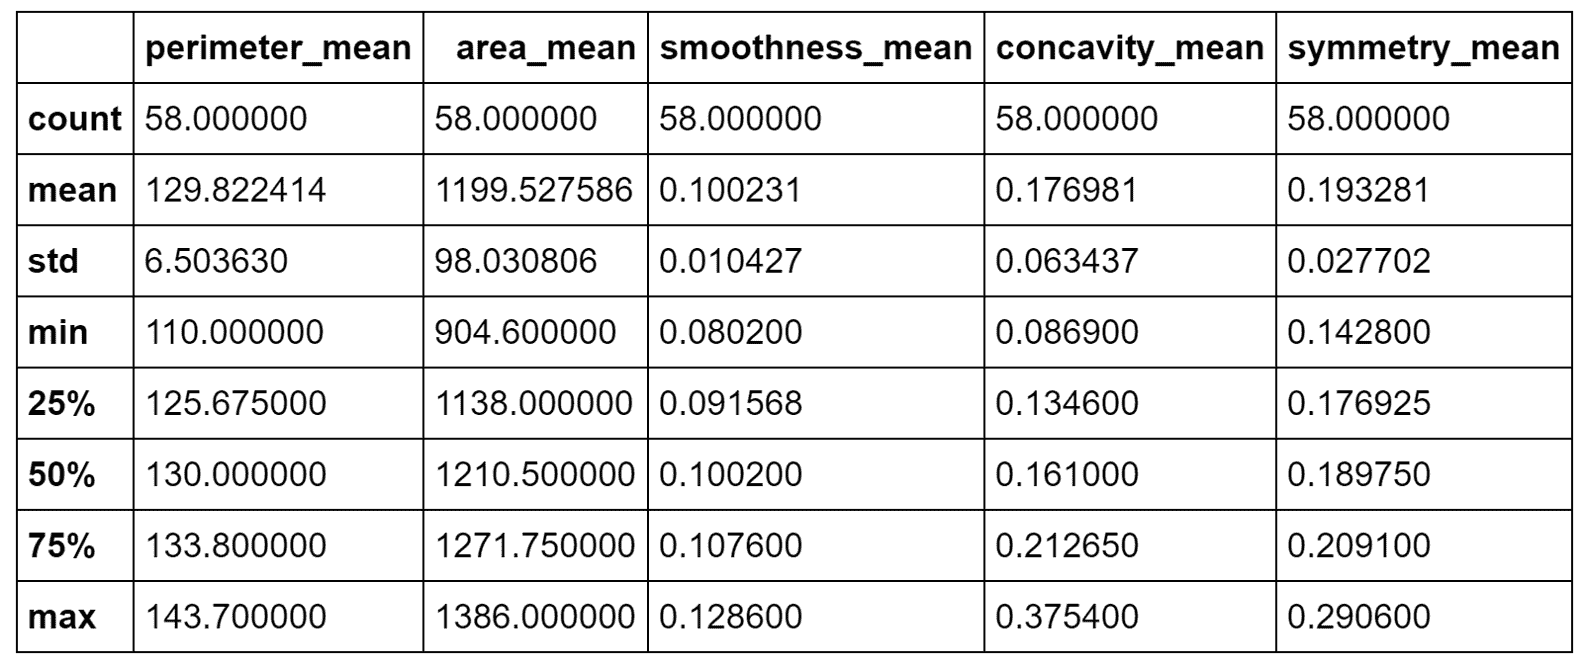

我强烈建议使用 Jupyter 笔记本(在这种情况下,命令必须仅是df.describe()),所有命令都将产生内联输出。 出于实际原因,在以下屏幕截图中,显示了表格输出的第一部分(包含八个属性):

数据集前八个属性的统计报告

当然,即使我们仅将注意力集中在子集上,我也请读者检查所有属性的值。 特别是,我们需要观察前八个属性之间存在的不同尺度。 标准差的范围是 0.01 到 350,这意味着仅由于一个或两个属性,许多向量可能极其相似。 另一方面,使用方差缩放对值进行归一化将赋予所有属性相同的责任(例如143.5和2501之间的界限为area_mean,而0.05和smoothness_mean之间的界限为smoothness_mean。 强迫它们具有相同的方差会影响因素的生物学影响,并且由于我们没有任何具体的指示,因此我们没有授权做出这样的选择)。 显然,某些属性在聚类过程中将具有更高的权重,我们将它们的主要影响视为与上下文相关的条件。

恶性群集的统计描述

根据事实,我们知道所有这些样本都是恶性的,但是我们可以尝试确定一个规则。 area_mean / perimeter_mean之比约为9.23,相对于平均值,相对标准差非常小。 这意味着这些样本在非常狭窄的范围内代表了扩展的肿瘤。 而且,concavity_mean和symmetry_mean均大于总值。 因此(在不进行科学合理分析的前提下),我们可以得出结论,分配给这些群集的样本代表了已经进入晚期的非常糟糕的肿瘤。

结果显示在以下屏幕截图中:

良性群集的统计描述

在这种情况下,比 area_mean / perimeter_mean 约为4.89,但是area_mean具有较大的标准差(实际上,其最大值约为410)。 concavity_mean相对于前一个非常小(即使具有近似相同的标准差),而symmetry_mean几乎相等。 从这个简短的分析中,我们可以推断出symmetry_mean不是判别特征,而concavity_mean的比值area_mean / perimeter_mean小于5.42(考虑最大值)。 小于或等于0.04应当保证良性结果。 由于concavity_mean可以达到非常大的最大值(大于与恶性样本相关的最大值),因此有必要考虑其他特征,以便确定是否应将其值视为警报。 但是,我们可以得出结论,说属于这些群集的所有样本都是良性的,错误概率可以忽略不计。 我想重复一遍,这不是真正的分析,而是更多的练习,在这种情况下,数据科学家的主要任务是收集可以支持结论的上下文信息。 即使存在基本事实,该验证过程也始终是强制性的,因为根本原因的复杂性可能导致完全错误的陈述和规则。